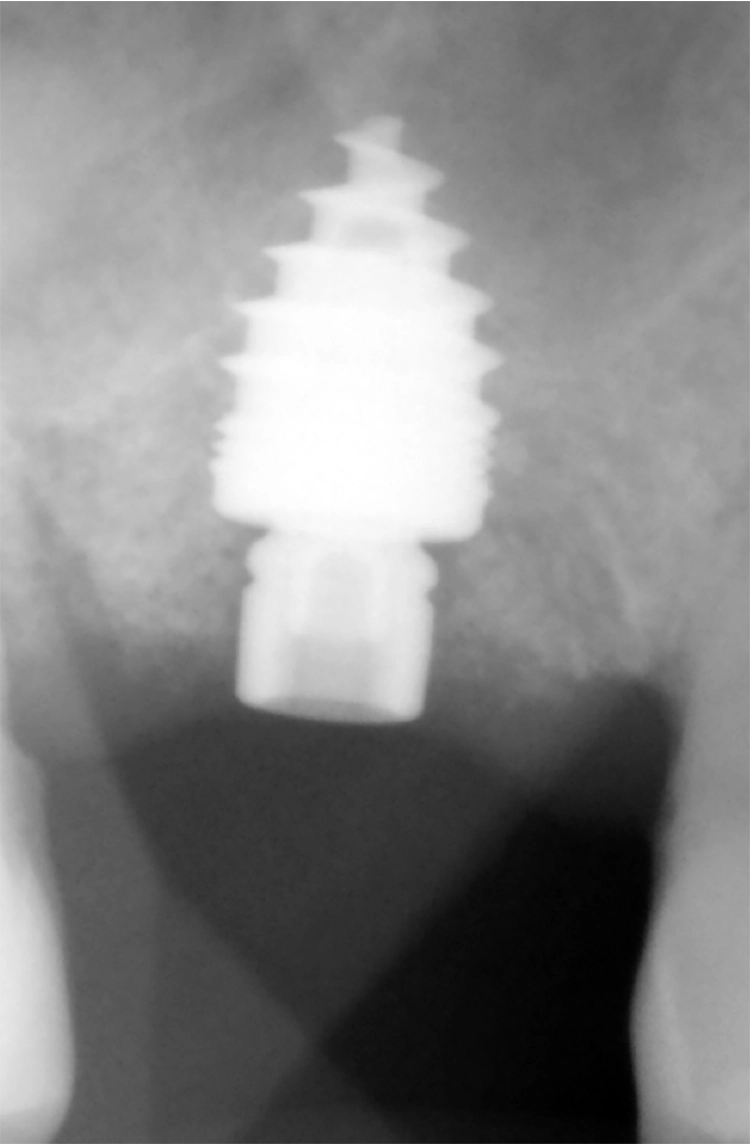

Nach Abnahme des Shuttles wird das Titan-Klebebasis-Abutment mit CEREC-Krone in das Implantat mit 30 Ncm verschraubt fixiert (Abb. 34-37).

Dr. Nedjat